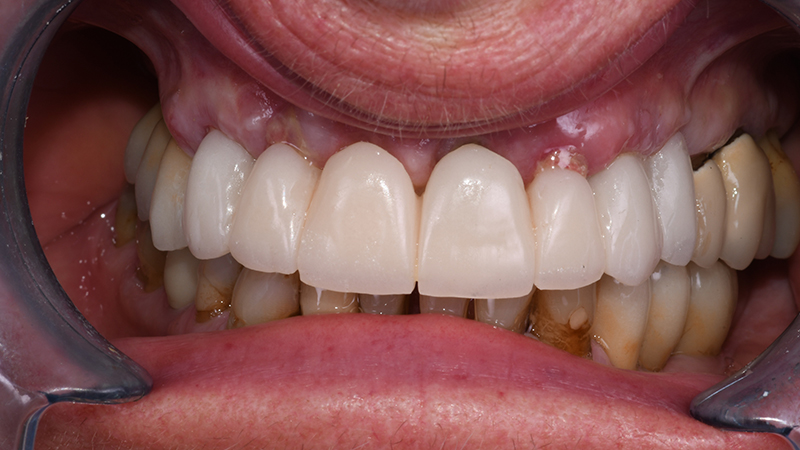

Le fixtures implantari sono state inserite seguendo il planning pre-chirurgico (Figs. 10, 11) in posizione 13-21-23-24. Lo spazio presente tra la componente vestibolare di ciascun impianto e l’osso vestibolare (jumping distance) e gli alveoli post-estrattivi non riceventi impianti, hanno ricevuto l’innesto di sostituto osseo xenogenico collagenato di origine suina (The Graft, Purgo, Challans, Francia) (Figs. 12, 13, 14) dopo aver posizionato i Multi-Unit abutment (MUA). La protesi provvisoria è stata avviata entro 24 ore dal termine della chirurgia (Figs. 15, 16).

Visione frontale intra-orale dopo applicazione di protesi provvisoria a carico immediato

Fig. 15 - Visione frontale intra-orale dopo applicazione di protesi provvisoria a carico immediato